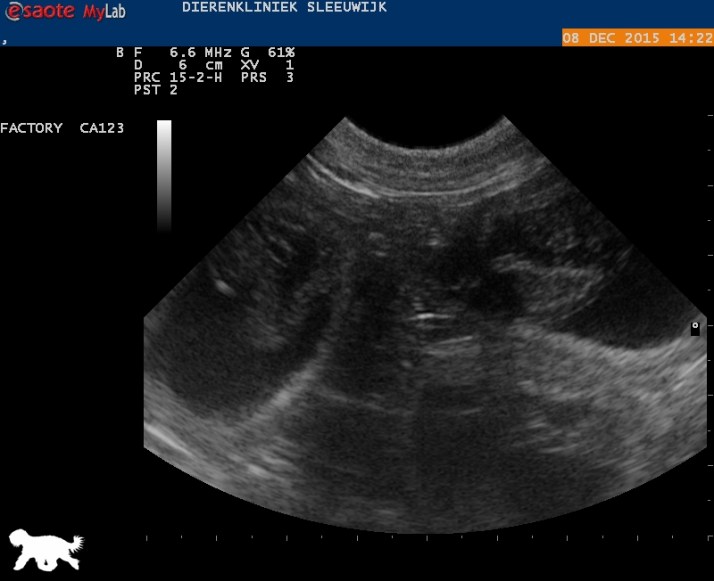

Hier tussen de witte kruisjes een heel pupje, 1.97 cm